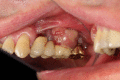

Peri-implant inflammations represent serious diseases after dental implant treatment, which affect both the surrounding hard and soft tissue. Due to prevalence rates up to 56%, peri-implantitis can lead to the loss of the implant without multilateral prevention and therapy concepts. Specific continuous check-ups with evaluation and elimination of risk factors (e.g. smoking, systemic diseases and periodontitis) are effective precautions. In addition to aspects of osseointegration, type and structure of the implant surface are of importance. For the treatment of peri-implant disease various conservative and surgical approaches are available. Mucositis and moderate forms of peri-implantitis can obviously be treated effectively using conservative methods. These include the utilization of different manual ablations, laser-supported systems as well as photodynamic therapy, which may be extended by local or systemic antibiotics. It is possible to regain osseointegration. In cases with advanced peri-implantitis surgical therapies are more effective than conservative approaches. Depending on the configuration of the defects, resective surgery can be carried out for elimination of peri-implant lesions, whereas regenerative therapies may be applicable for defect filling. The cumulative interceptive supportive therapy (CIST) protocol serves as guidance for the treatment of the peri-implantitis. The aim of this review is to provide an overview about current data and to give advices regarding diagnosis, prevention and treatment of peri-implant disease for practitioners.